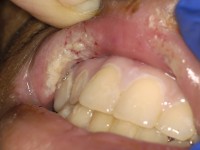

3.

Orofaciale manifestaties van Crohn.Afwijkingen van het

mondslijmvlies en de lippen kunnen geassocieerd voorkomen bij Crohn en soms

er aan voorafgaan. Circa 5-20% van de Crohn patiënten hebben orofaciale

afwijkingen zoals

stomatitis aphtosa (aften), pyostomatitis vegetans,

cheilitis angularis, mucosale ulcera, multipele noduli op het wangslijmvlies

of op de gingiva (cobblestoning of the buccal mucosa), en pijnlijk

geïndureerde fissuren in de onderlip. Stomatitis aphthosa wordt vooral bij

Crohn gezien en minder bij colitis ulcerosa; het kunnen minor of major aften

zijn.